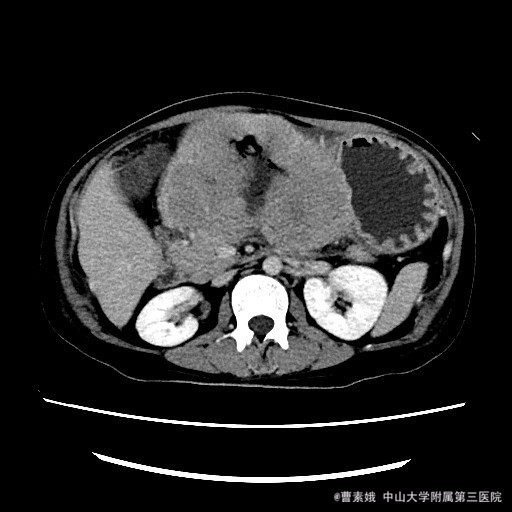

患者:女 37岁 主诉:发现腹部包块伴恶性、呕吐1月余 病史:患者平素一直有胃部不适,偶有胃痛、饱胀感不适,一直口服药物治疗,未见明显好转,1月前自觉腹部包块,并出现恶性、呕吐。呕吐为胃内容物。

查体:左上腹触及一包块,较柔软,余未特殊。 辅助检查:全腹CT平扫+增强示:胃体至胃窦部胃壁弥漫性增厚并软组织肿块,考虑淋巴瘤可能性大。

入院诊断:胃淋巴瘤(?) 治疗:诊断:胃淋巴瘤(?) 治疗:入院后(胃部肿物)送检组织镜下见胃粘膜固有层及肌层结构破坏,并见中等偏大异形淋巴样细胞弥漫浸润,局部成片分布,细胞具有异型性,可见核仁,核分裂象易见,结合免疫组化结果,符合高级别B细胞源性淋巴瘤,考虑滤泡淋巴瘤(FL3b)。组织少,肿瘤成份少,不完全排除弥漫大B细胞性淋巴瘤(生发中心亚型)。建议结合临床。排除手术禁忌症后,于腹腔镜下胃大部分切除术 。 术程顺利,患者恢复较好,建议其进一步化疗,患者表示拒绝后出院。